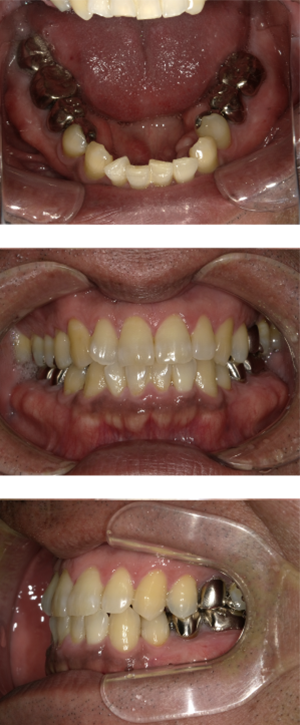

50代 女性 インプラント治療(GBR・ソケットリフト)

| 年代・性別 | 50代・女性 |

|---|---|

| 主訴 | Brの歯が取れそうなため、インプラントに変えたい。 |

| 部位 | 左下567 左上④5⑥ 右上67 |

| 治療期間 | 約3年9ヶ月 |

| 費用 | ¥3,224,500(税込) |

| 副作用・リスク |

|